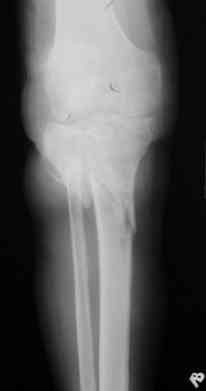

Р-граммы за март и апрель

> Р-граммы за март и апрель